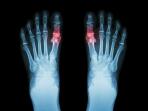

Bệnh gút là một dạng viêm khớp đặc biệt, được đặc trưng bởi các đợt cấp tính với những cơn đau dữ dội, sưng tấy, đỏ và đau nhức ở các khớp bị ảnh hưởng. Tình trạng suy nhược này chủ yếu phát sinh từ sự tích tụ axit uric trong cơ thể, dẫn đến sự hình thành các tinh thể sắc nhọn, giống như kim trong và xung quanh các khớp. Mặc dù nó có thể ảnh hưởng đến nhiều khớp trên khắp cơ thể, nhưng bệnh gút thường nhắm mục tiêu vào khớp ở gốc ngón chân cái, một triệu chứng đặc trưng thường dẫn đến chẩn đoán nhanh chóng. Tuy nhiên, điều quan trọng không kém là phải nhận ra rằng các khu vực khác như đầu gối, cổ tay và khuỷu tay cũng có thể trở thành địa điểm của những đợt bùng phát đau đớn này.

Bệnh gút Bệnh gút trông như thế nào Bệnh gút là một loại viêm khớp cụ thể do các tinh thể axit uric trong khớp và các mô khác của bạn gây ra. Cơ thể bạn thường tạo ra axit uric khi nó phân hủy purin. Purin được tìm thấy trong một số loại thực phẩm và đồ uống. Thông thường, thận của bạn lọc axit uric ra khỏi máu của bạn. Tuy nhiên, nếu bạn bị bệnh gút, thận của bạn không loại bỏ đủ axit uric qua đường tiểu. Khu vực bị ảnh hưởng phổ biến nhất là khớp ngón chân cái, nhưng các bộ phận khác của bàn chân và cơ thể (chẳng hạn như đầu gối, cổ tay và khuỷu tay) cũng có thể bị ảnh hưởng. Bệnh gút là dạng viêm khớp phổ biến nhất ở nam giới trên 40 tuổi. Ngày 6 tháng 6 năm 2021